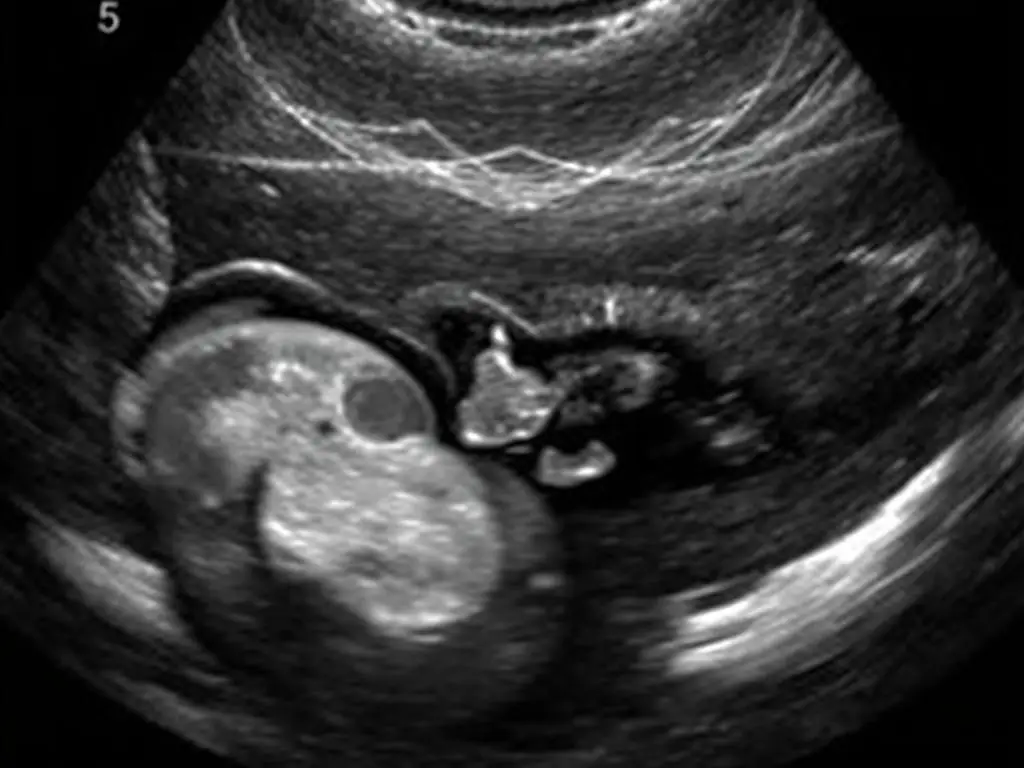

Rozwój narządów płciowych płodu w 12 tygodniu ciąży – wczesne stadium różnicowania

Jedno z najczęstszych pytań, które zadają przyszli rodzice podczas USG w 12 tygodniu ciąży, dotyczy możliwości określenia płci dziecka. W tym okresie narządy płciowe zewnętrzne zaczynają się już różnicować, jednak ich rozwój jest jeszcze na wczesnym etapie [12].

U płodów płci męskiej w 12 tygodniu ciąży rozpoczyna się produkcja testosteronu, który wpływa na kształtowanie się męskich narządów płciowych. U płodów płci żeńskiej, przy braku testosteronu, rozwijają się żeńskie narządy płciowe. Jednak na tym etapie ciąży różnice anatomiczne są jeszcze niewielkie i trudne do jednoznacznego określenia podczas standardowego badania USG [13].

Doświadczony lekarz może czasem podjąć próbę określenia płci dziecka już w 12 tygodniu ciąży, jednak dokładność takiej oceny jest ograniczona. Szansa na prawidłowe określenie płci w tym okresie wynosi około 70-75%. Znacznie bardziej wiarygodne jest badanie wykonane w późniejszym okresie, najczęściej podczas USG połówkowego około 20. tygodnia ciąży, gdy narządy płciowe są już dobrze wykształcone [14].

Obraz USG płodu w 12 tygodniu – widoczny zawiązek narządów płciowych, trudny do jednoznacznej interpretacji

Warto pamiętać, że określenie płci dziecka podczas badania USG nie jest celem medycznym tego badania. Priorytetem jest ocena prawidłowego rozwoju płodu i wykrycie ewentualnych nieprawidłowości. Jeśli bardzo zależy Ci na wcześniejszym poznaniu płci dziecka, możesz rozważyć wykonanie nieinwazyjnych testów prenatalnych (NIPT), które analizują DNA płodu obecne w krwi matki i pozwalają określić płeć z dokładnością powyżej 99% już od 10. tygodnia ciąży [15].